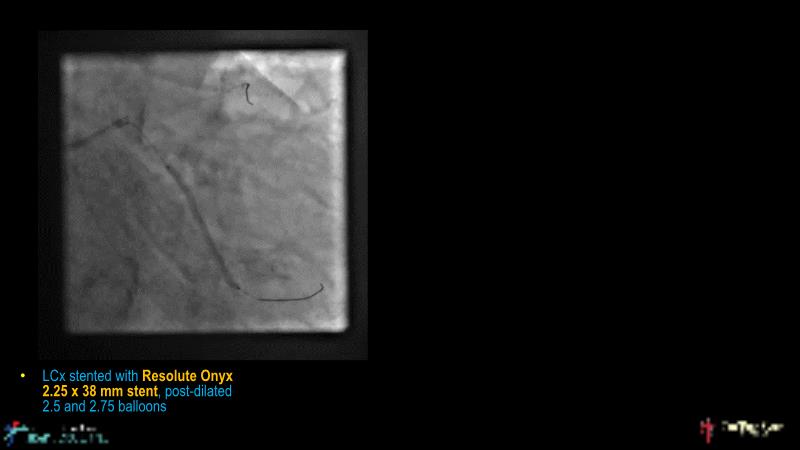

Watch this case-based session to follow discussion about how to choose between DES & DCB, how both can be complementary in diffuse disease as well as in complex PCI, and how physiology and imaging can help guiding PCI, and follow a patient's treatment live.

- To learn the tips and tricks in performing complex PCI intervention with DES and/or DCB

- To discuss cases when DES and DCB are complementary

- To discover strategies to simplify complex PCI cases with the latest DES and DCB